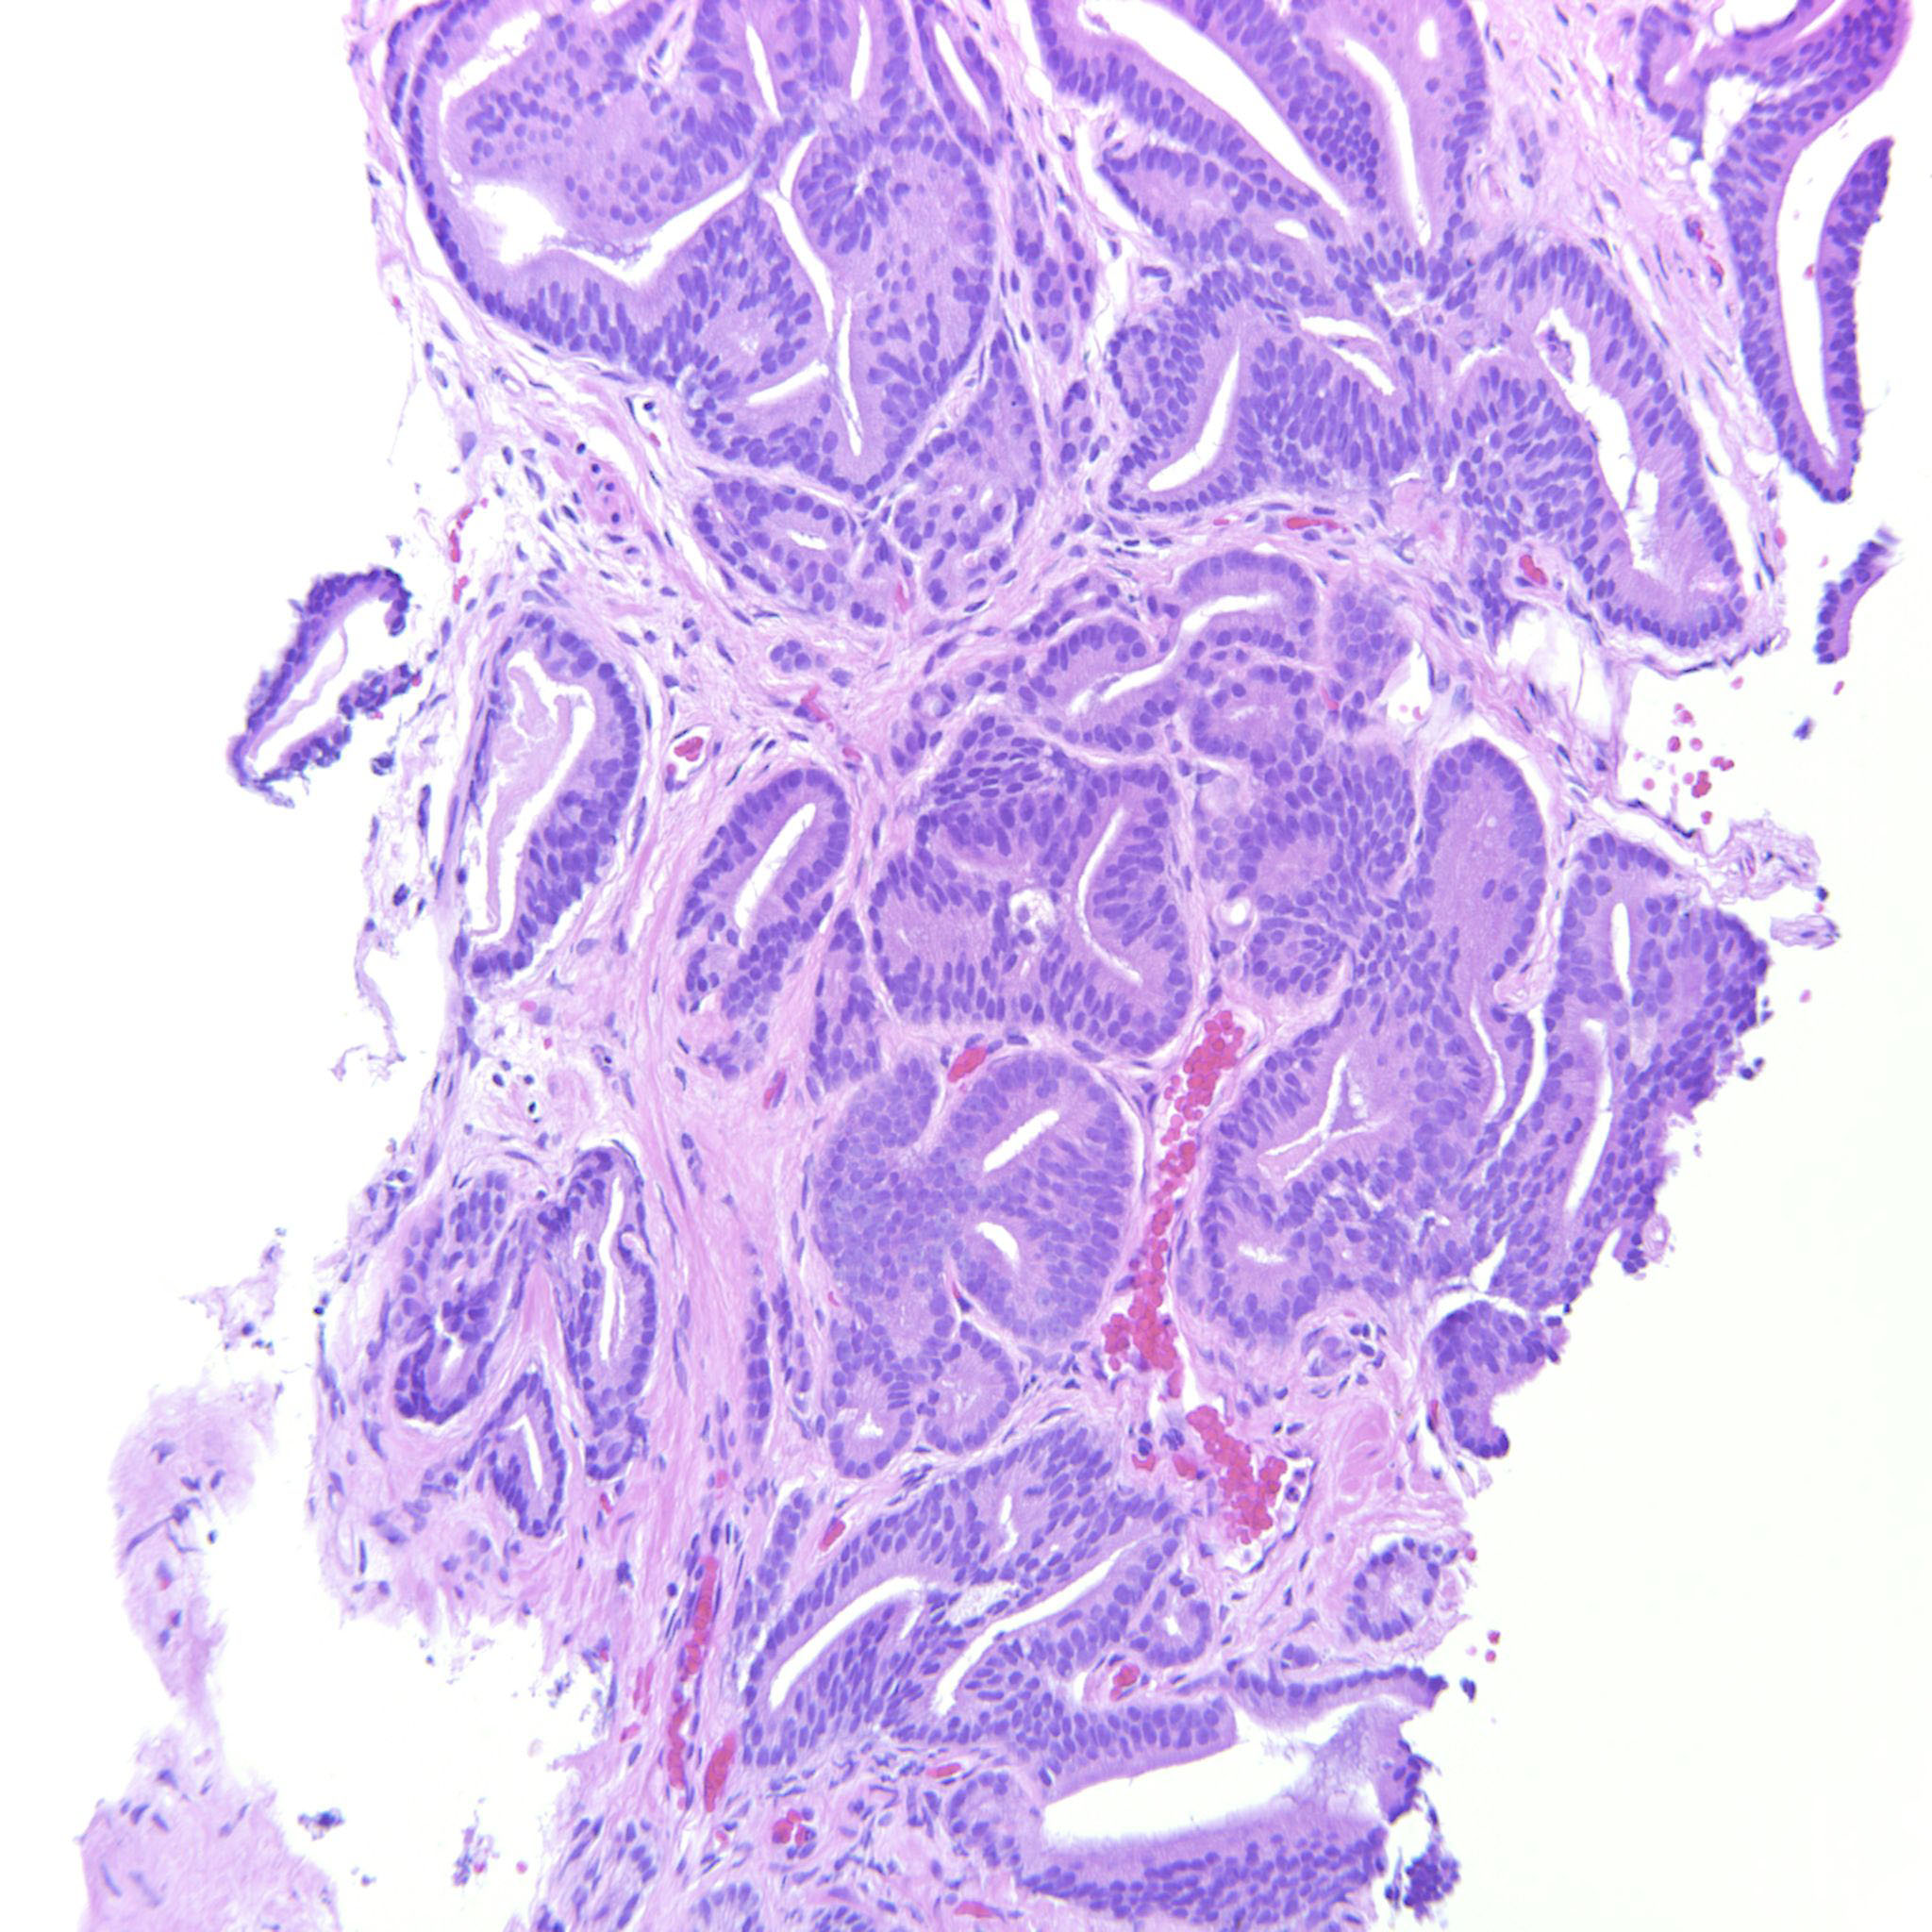

Consensus grade: GS 3+4=7 (ISUP 2)

Case description (by case creator):

A lot of the tumor is GP3 but there are also a couple of cribriform glands. The epithelium is tall columnar, sometimes with elongated nuclei but the tumor does not have other features of ductal adenocarcinoma and should probably be considered a variant of acinar adenocarcinoma of the prostate.